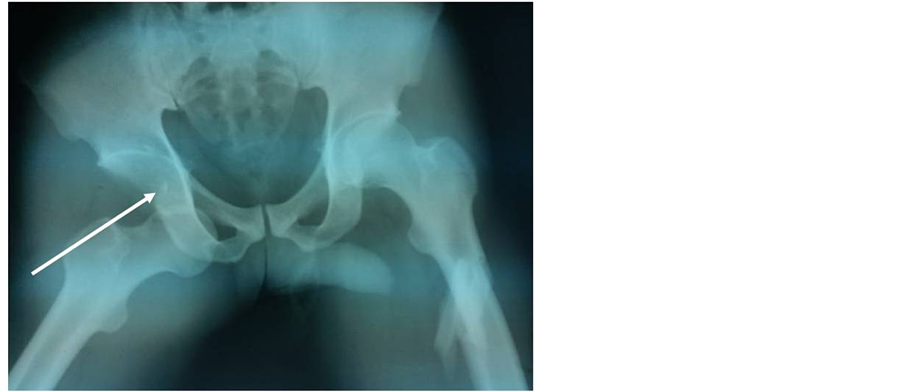

Plain X-rays confirmed a left subtrochanteric fracture and a right obturator dislocation of the hip with an intra-articular incarcerated fragment (Figure 3). Closed reduction of the dislocated hip and surgical treatment of the left subtrochanteric fracture by a Küntscher intramedullary nail; were performed the same day the patient was admitted. Post-reduction radiographs showed an articular gap widening with a defect in the superior lateral femoral head (Figure 4). A confirmation CT scan demonstrated an intra-articular incarcerated fragment (Figure 5). An arthroscopic extraction was warranted, but due to inadequate hospital equipment and patient financial hardship; the patient did not receive appropriate care. Fifteen months later; Mr. SA presented with a control X-ray showing early signs of coxarthrosis and peri-articular ossifications (Figure 6).

Figure 3. Anteroposterior X-ray of the pelvis showing a right obturator dislocation with an intra-articular incarcerated fragment (arrow) and a left subtrochanteric fracture (patient 3).